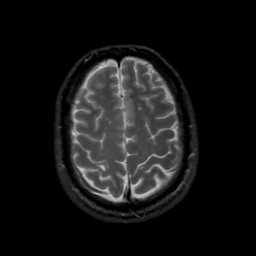

MR Study #18, July 21, 1991 -- Slice #40